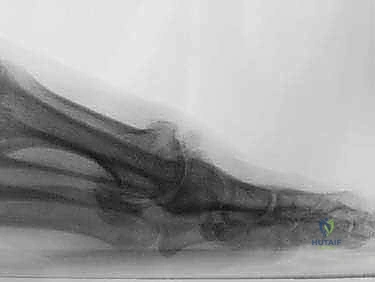

لفهم طبيعة مرض إبهام القدم المتصلب، يجب أولاً أن نفهم التصميم الهندسي المذهل للقدم البشرية. يقع المفصل المشطي السلامي الأول (First MTP Joint) في قاعدة إصبع القدم الكبير. يربط هذا المفصل بين عظمة المشط الأولى (Metatarsal) وعظمة السلامية القريبة (Proximal Phalanx) للإصبع الكبير.

عندما يُصاب الشخص بـ "إبهام القدم المتصلب"، تتآكل هذه الطبقة الغضروفية تدريجياً. ومع فقدان هذه الوسادة الواقية، تبدأ العظام في الاحتكاك ببعضها البعض مباشرة، مما يؤدي إلى نمو نتوءات عظمية (Osteophytes) حول المفصل، وهي التي تسبب التيبس والألم وتعيق الحركة بشكل كامل.

## الأعراض السريرية: كيف تعرف أنك مصاب بإبهام القدم المتصلب؟ تتطور أعراض إبهام القدم المتصلب بشكل خفي وتدريجي. تجاهل الأعراض المبكرة يؤدي حتماً إلى تفاقم الحالة. إليك العلامات التحذيرية التي يجب ألا تتجاهلها: 1. **ألم في قاعدة الإبهام:** ألم يزداد سوءاً عند المشي، الجري، أو الوقوف لفترات طويلة. 2. **تيبس ومحدودية الحركة:** صعوبة بالغة في ثني إصبع القدم لأعلى أو لأسفل. 3. **تورم والتهاب:** انتفاخ واحمرار حول المفصل، خاصة في الجزء العلوي منه. 4. **نتوء عظمي مرئي (Bunion-like):** ظهور كتلة صلبة أو نتوء عظمي أعلى المفصل، مما يسبب احتكاكاً مؤلماً مع الحذاء. 5. **تغير في نمط المشي:** بسبب الألم، يبدأ المريض في المشي على الحافة الخارجية للقدم، مما يؤدي إلى آلام ثانوية في الركبة، الورك، أو أسفل الظهر. ### جدول (1): مراحل تطور إبهام القدم المتصلب (تصنيف كوفلين وشورناس) | المرحلة | وصف الغضروف والأشعة السينية | الأعراض السريرية | نطاق الحركة (الانثناء لأعلى) | | :--- | :--- | :--- | :--- | | **المرحلة 0** | الغضروف سليم، الأشعة طبيعية. | تيبس طفيف، ألم متقطع. | 40 - 60 درجة | | **المرحلة 1** | تضيق طفيف في المسافة المفصلية، نتوءات عظمية صغيرة. | ألم عند الحد الأقصى للحركة، تورم عرضي. | 30 - 40 درجة | | **المرحلة 2** | تضيق معتدل، نتوءات عظمية واضحة في الجزء العلوي. | ألم مستمر عند المشي، صعوبة في ارتداء أحذية معينة. | 10 - 30 درجة | | **المرحلة 3** | تآكل شديد للغضروف، نتوءات عظمية كبيرة محيطة بالمفصل. | ألم شديد ومستمر، تيبس ملحوظ، ألم عند ملامسة النتوءات. | أقل من 10 درجات | | **المرحلة 4** | غياب كامل للغضروف (عظم يحك في عظم). | ألم مبرح حتى أثناء الراحة أو عند تحريك المفصل سلبياً. | شبه معدومة |  ## رحلة التشخيص الدقيق مع الأستاذ الدكتور محمد هطيف يعتبر التشخيص الدقيق حجر الأساس لنجاح أي خطة علاجية. في عيادة الأستاذ الدكتور محمد هطيف في صنعاء، يتم اتباع بروتوكول تشخيصي صارم يعتمد على الأمانة الطبية والتقييم الشامل: * **الفحص السريري الدقيق:** يقوم الدكتور هطيف بتقييم نطاق الحركة، تحديد مواقع الألم الدقيقة، وفحص نمط المشي (Gait Analysis). * **التصوير بالأشعة السينية (X-rays):** وهي الأداة الذهبية لتأكيد التشخيص. يتم أخذ صور للأشعة في وضعية الوقوف (تحمل الوزن) لتقييم مدى تضيق المسافة المفصلية وحجم النتوءات العظمية. * **التصوير بالرنين المغناطيسي (MRI):** يُطلب في حالات نادرة جداً، وذلك لتقييم الأنسجة الرخوة أو إذا كان هناك شك في وجود نخر انعدام الدم (Avascular Necrosis) في رأس عظمة المشط.  ## الخيارات العلاجية: من التحفظي إلى التدخل الجراحي لا يتسرع الأستاذ الدكتور محمد هطيف، بخبرته التي تتجاوز العشرين عاماً، في اتخاذ قرار الجراحة. وفقاً لمبدأ الأمانة الطبية الصارمة، يتم استنفاد كافة الحلول التحفظية أولاً، خاصة في المراحل المبكرة (المرحلة 1 و 2). ### أولاً: العلاج التحفظي (غير الجراحي) 1. **تعديل الأحذية:** استخدام أحذية ذات نعل صلب (Stiff-soled shoes) أو نعل متأرجح (Rocker-bottom) لتقليل حركة المفصل أثناء المشي وتخفيف الضغط. 2. **الأدوية ومضادات الالتهاب:** استخدام مضادات الالتهاب غير الستيرويدية (NSAIDs) لتخفيف الألم والتورم. 3. **الحقن الموضعية:** حقن الكورتيزون داخل المفصل لتقليل الالتهاب الحاد، أو حقن البلازما الغنية بالصفائح الدموية (PRP) لتحفيز التئام الأنسجة. 4. **العلاج الطبيعي:** تمارين محددة للحفاظ على مرونة المفصل وتقوية العضلات المحيطة.  ### ثانياً: التدخلات الجراحية المتاحة عندما تفشل العلاجات التحفظية وتصبح جودة حياة المريض مهددة (عادة في المراحل 3 و 4)، يصبح التدخل الجراحي ضرورة حتمية. هناك عدة خيارات جراحية، ولكل منها دواعي استعمال: 1. **استئصال النتوءات العظمية (Cheilectomy):** يُستخدم في المراحل المبكرة والمتوسطة. يتم إزالة النتوءات العظمية من أعلى المفصل لتحرير الحركة. 2. **إيثاق المفصل (Arthrodesis/Fusion):** دمج العظمتين معاً باستخدام براغي أو شرائح. يزيل الألم نهائياً ولكنه يلغي حركة المفصل تماماً، مما يجعله غير مفضل للرياضيين أو النساء اللواتي يرغبن في ارتداء أحذية بكعب. 3. **استبدال المفصل الصناعي (Joint Replacement):** استبدال المفصل بمفصل معدني أو بلاستيكي. قد يتعرض للتآكل أو الفشل بمرور الوقت. 4. **جراحة تبديل المفصل بالكبسولة (Capsular Interposition Arthroplasty):** **وهي الطفرة الطبية التي نركز عليها هنا**، والتي يبرع فيها الأستاذ الدكتور محمد هطيف.  ### جدول (2): مقارنة شاملة بين إيثاق المفصل وجراحة تبديل المفصل بالكبسولة | وجه المقارنة | إيثاق المفصل (Fusion) | تبديل المفصل بالكبسولة (Interposition) | | :--- | :--- | :--- | | **الهدف الأساسي** | القضاء التام على الألم عبر دمج العظام. | القضاء على الألم **مع الحفاظ على حركة المفصل**. | | **حركة المفصل بعد الجراحة** | معدومة (المفصل ثابت تماماً). | محفوظة (حركة طبيعية أو شبه طبيعية). | | **المواد المستخدمة** | براغي وشرائح معدنية (تيتانيوم). | أنسجة الجسم الطبيعية (الكبسولة المفصلية). | | **المرونة في ارتداء الأحذية** | مقيدة (لا يمكن ارتداء الكعب العالي). | مرونة عالية (يمكن ارتداء أنواع مختلفة من الأحذية). | | **خطر رفض الجسم أو العدوى** | موجود (بسبب الأجسام الغريبة المعدنية). | شبه معدوم (لأن النسيج ذاتي من المريض). | | **المرشح المثالي** | كبار السن، ذوي النشاط المحدود جداً. | الشباب، الرياضيون، والأشخاص النشطون حركياً. |  ## التفوق الجراحي: ما هي جراحة تبديل المفصل بالكبسولة؟ جراحة تبديل المفصل بالكبسولة (Capsular Interposition Arthroplasty) هي تقنية جراحية متقدمة لإنقاذ المفصل. الفكرة العبقرية وراء هذه الجراحة هي استخدام أنسجة المريض نفسه كـ "وسادة" أو "حاجز" بين العظام التي فقدت غضروفها. بدلاً من دمج المفصل وإلغاء حركته، وبدلاً من إدخال مفصل صناعي قد يفشل بعد سنوات، يقوم الجراح باستخدام جزء من **الكبسولة المفصلية** (الغلاف النسيجي المحيط بالمفصل) أو الأوتار المجاورة، وتثبيتها فوق السطح العظمي المتآكل. هذا النسيج الحيوي يتحول بمرور الوقت إلى سطح أملس يمنع احتكاك العظام ببعضها، مما يزيل الألم ويسمح للمفصل بالانثناء بسلاسة.  ## خطوات الجراحة خطوة بخطوة مع الأستاذ الدكتور محمد هطيف تتطلب هذه الجراحة مهارة يدوية دقيقة وفهماً عميقاً للميكانيكا الحيوية للقدم. بفضل استخدام تقنيات الجراحة الميكروسكوبية وأدوات الجراحة الدقيقة، يضمن الدكتور هطيف أعلى نسب النجاح. إليك كيف تتم العملية: ### 1. التخدير والتحضير تُجرى العملية عادة تحت التخدير الموضعي أو النصفي، مع إعطاء المريض مهدئاً خفيفاً. يتم تعقيم القدم وتجهيز بيئة العمليات وفق أعلى معايير مكافحة العدوى. ### 2. الشق الجراحي الدقيق يتم إجراء شق جراحي طولي دقيق أعلى المفصل (Dorsal Incision). يحرص الدكتور هطيف على الحفاظ على الأعصاب الحسية الدقيقة والأوعية الدموية المحيطة بالمنطقة لتسريع الشفاء.  ### 3. استئصال النتوءات العظمية وتجهيز العظم يتم فتح الكبسولة المفصلية بعناية فائقة. بعد كشف المفصل، يقوم الجراح بإزالة جميع النتوءات العظمية (Osteophytes) التي تعيق الحركة. ثم يتم إزالة حوالي ربع إلى ثلث رأس عظمة المشط (Metatarsal Head Resection) لتوفير مساحة كافية للنسيج الجديد وتقليل الضغط داخل المفصل.  ### 4. تحضير الكبسولة (النسيج البيني) هذه هي الخطوة الأكثر دقة. يتم تحرير جزء من الكبسولة المفصلية العلوية (Dorsal Capsule) أو وتر العضلة الباسطة القصير (Extensor Hallucis Brevis)، وتشكيلها لتصبح سديلة (Flap) نسيجية قوية.  ### 5. التثبيت والخياطة (Interposition) يتم سحب هذه السديلة النسيجية وإدخالها في المسافة المفصلية الجديدة لتغطي نهاية العظمة المقطوعة بالكامل. يتم تثبيت هذا النسيج بإحكام باستخدام خيوط جراحية قوية تمر عبر ثقوب دقيقة يتم إحداثها في العظم، مما يضمن عدم تحرك النسيج من مكانه أثناء الحركة.  ### 6. التثبيت المؤقت والإغلاق في بعض الحالات، قد يتم استخدام سلك معدني دقيق (K-wire) لتثبيت المفصل مؤقتاً في وضع مستقيم لمدة أسبوعين إلى ثلاثة أسابيع للسماح للأنسجة بالالتئام الأولي. بعد ذلك، يتم إغلاق الجلد بخياطة تجميلية دقيقة وتطبيق ضمادة ضاغطة ناعمة.  ## دليل إعادة التأهيل الشامل: طريقك نحو الشفاء التام نجاح الجراحة لا يعتمد فقط على مهارة الجراح داخل غرفة العمليات، بل يعتمد بنسبة 50% على التزام المريض ببرنامج إعادة التأهيل. يقدم فريق الأستاذ الدكتور محمد هطيف خطة تعافي مفصلة: * **الأسابيع 1 - 2 (مرحلة الحماية التامة):** * الراحة التامة مع رفع القدم لتقليل التورم. * ارتداء حذاء جراحي خاص ذو نعل صلب. * يُ ---